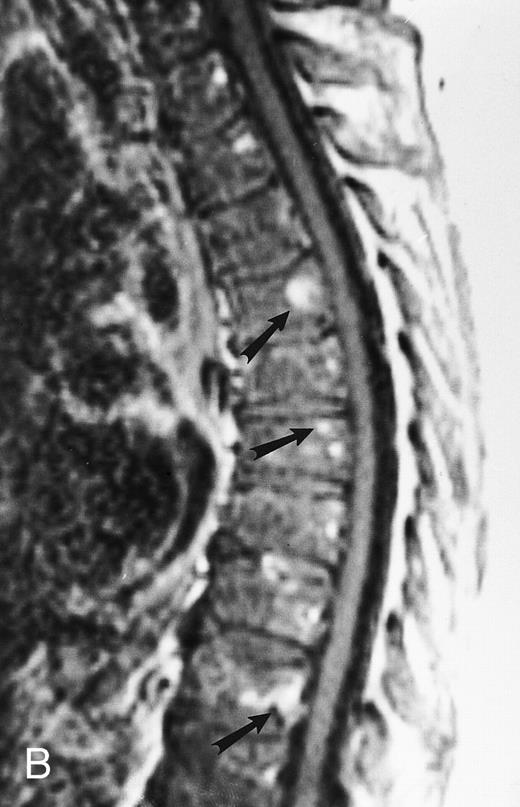

T1-weighted (500/11, TR/TE) sagittal MR images of the lumbosacral spine in a 45-year-old woman before (A) and 40 days after (B) bone marrow transplantation for multiple myeloma. There is a diffuse MR pattern of marrow involvement in (A) (bone marrow plasma cells, 50%; monoclonal protein, 6.0 g/dL). On the posttreatment image, there is definite reinstitution of fatty marrow in the spine and, in particular, around the basivertebral veins, in keeping with partial response to treatment (bone marrow plasma cells, 0.5%; monoclonal protein, 1.6 g/dL).